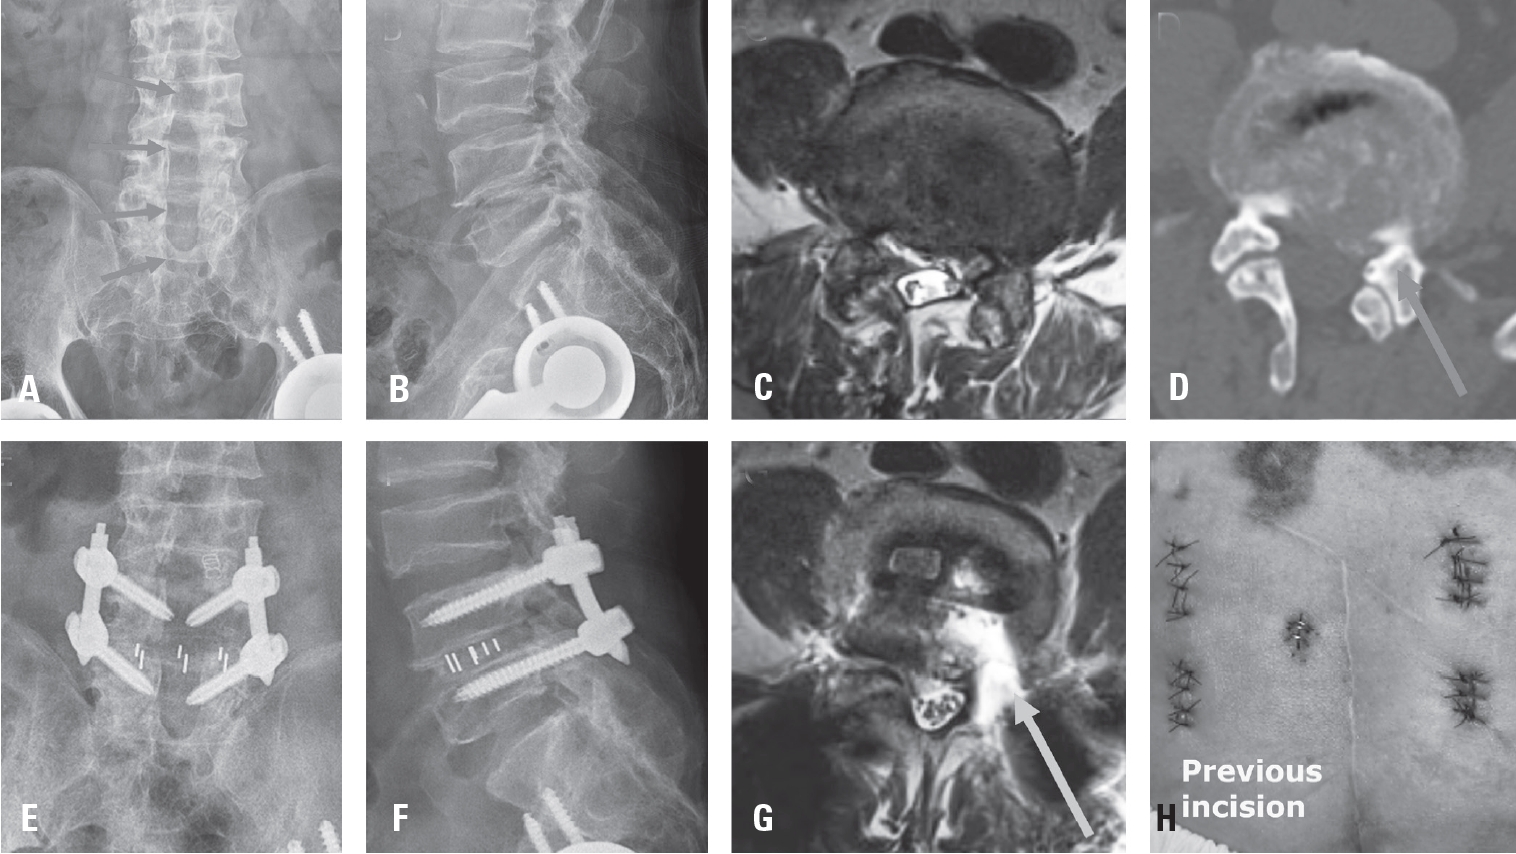

Fig. 2.

Schematic illustration of the extraforaminal working corridor for biportal endoscopic revision extraforaminal lumbar interbody fusion (BE-REFLIF) in a previously decompressed segment. (A) Targeting of the remnant inferior articular process (IAP) and the superior articular process (SAP) to define the bony boundaries of the working corridor. (B) Illustration of the established extraforaminal corridor used for interbody cage insertion. (C) Visualization of the opened disc space between the exiting nerve root and the traversing nerve root after adequate decompression. (D) Measurement of the distance between the traversing and exiting nerve roots, demonstrating a minimum required safety margin of 15 mm to allow safe insertion of the interbody cage.

Representative case of biportal endoscopic revision extraforaminal lumbar interbody fusion (BE-REFLIF). A 66-year-old man with recurrent left-sided radicular pain 10 years after extensive posterior decompression. (A, B) Preoperative radiographic images demonstrating extensive laminectomy on the left side at the L3–4, L4–5, and L5–S1 levels. (C) Preoperative axial MRI showing adhesive epidural fibrosis and a recurrent disc fragment compressing the left exiting nerve root. (D) Axial CT image demonstrating the previous hemilaminectomy site at the L4–5 level. (E, F) Postoperative radiographs showing proper interbody cage placement and restoration of disc height. (G) Postoperative axial MRI demonstrating adequate neural decompression and appropriate cage positioning. (H) Revision incision placed to avoid the previous surgical incision.BE-REFLIF, biportal endoscopic revision extraforaminal lumbar interbody fusion; CT, computed tomography; MRI, magnetic resonance imaging.